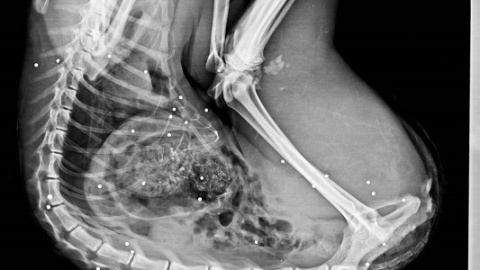

En 2017 han muerto 34 linces en España por la acción humana

El cuerpo del animal fue identificado por los técnicos, que tras un primer análisis ocular, no apreciaron indicios de violencia. Fue trasladado al Centro de Análisis y Diagnóstico de la Fauna Silvestre de la Junta de Andalucía (CAD) donde se le está practicando la necropsia. Según han desvelado los primeros datos de la misma, en el cuerpo de esta lince se han observado unos 35 plomos, lo que viene a constatar que detrás de esta muerte está la acción humana.